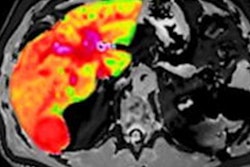

Image analysis software developer Perspectum Diagnostics is expanding development of its artificial intelligence (AI) algorithm to include cardiac and lung imaging.

The company has launched two new studies: Coverscan and Modify. The studies involve aortic and cardiac imaging with MRI and are particularly aimed at better understanding the impact and progression of COVID-19 disease (Coverscan) and diabetes (Modify).

The studies are part of Perspectum's further development of its Atlas metabolic software suite, according to the firm.